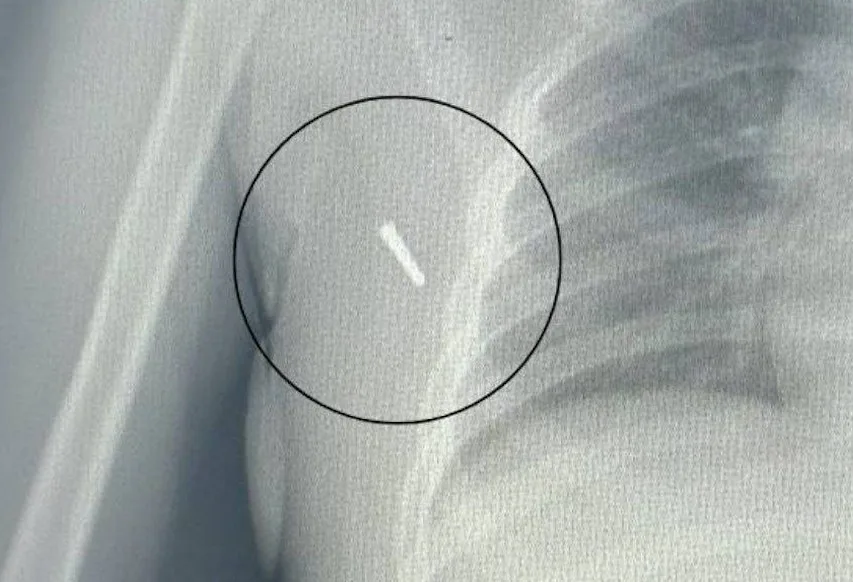

Ребёнка в срочном порядке доставили во Владивосток, где врачи провели операцию и извлекли обломок. К счастью, серьёзных последствий удалось избежать.